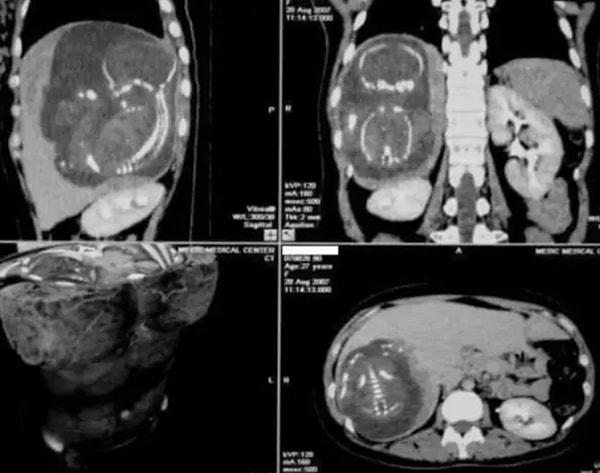

17. «Сегодня я узнала, что эмбрион может прикрепиться к печени и просто... и у вас будет внематочная беременность прямо около печени»